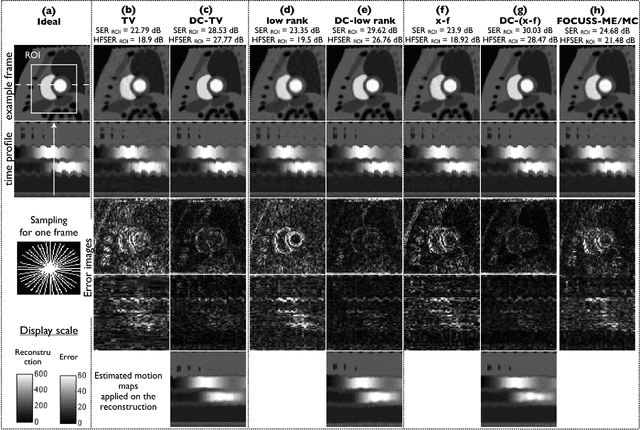

Abstract:We propose a novel deformation corrected compressed sensing (DC-CS) framework to recover dynamic magnetic resonance images from undersampled measurements. We introduce a generalized formulation that is capable of handling a wide class of sparsity/compactness priors on the deformation corrected dynamic signal. In this work, we consider example compactness priors such as sparsity in temporal Fourier domain, sparsity in temporal finite difference domain, and nuclear norm penalty to exploit low rank structure. Using variable splitting, we decouple the complex optimization problem to simpler and well understood sub problems; the resulting algorithm alternates between simple steps of shrinkage based denoising, deformable registration, and a quadratic optimization step. Additionally, we employ efficient continuation strategies to minimize the risk of convergence to local minima. The proposed formulation contrasts with existing DC-CS schemes that are customized for free breathing cardiac cine applications, and other schemes that rely on fully sampled reference frames or navigator signals to estimate the deformation parameters. The efficient decoupling enabled by the proposed scheme allows its application to a wide range of applications including contrast enhanced dynamic MRI. Through experiments on numerical phantom and in vivo myocardial perfusion MRI datasets, we demonstrate the utility of the proposed DC-CS scheme in providing robust reconstructions with reduced motion artifacts over classical compressed sensing schemes that utilize the compact priors on the original deformation un-corrected signal.